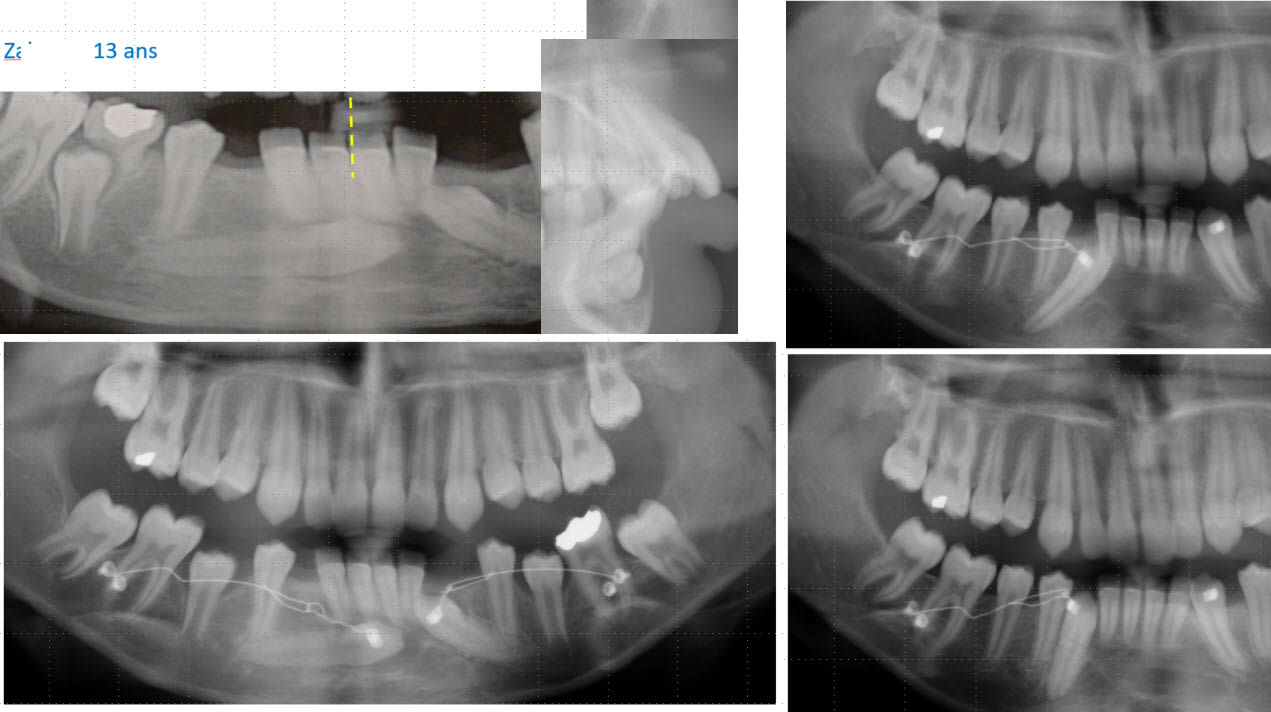

L'apex de la 43 est en bonne position, ce qui veut dire que tu n'a qu'a faire un mouvement de tipping pour redresser la dent.

J'ai quasi le même cas en cour :-) .

La patiente avait besoins d'un traitement ortho ( une canine impacté en haut aussi ) donc j'ai intégré la traction avec l'appareillage et pas besoin d'utiliser de minivisse.

Par contre c'est long prévoir minimum un ans pour redresser la canine.

Plus d'un ans pour en arriver là.

Ca y est 8 mois plus tard j'ai put poser un bracket dessus :-) .

Pour ton cas ça devrait aller plus vite. Quand j'ai commencé ce cas je n'avais pas le bon matériel disponible ( aujourd'hui ça serait la technique à Dancha direct ) , j'ai bricolé différent stytem mais il y a eux de la casse et plusieurs réparation on était nécessaire.

Enfin gros plaisir quand j'ai collé le bracket sur cette dent.

Sur ce cas très honnêtement je n'avais pas imaginer que redresser cette canine prendrait si longtemps. Mécaniquement très simple du à la bonne position de l'apex, simple mouvement de tipping mais putain 2 ans ...